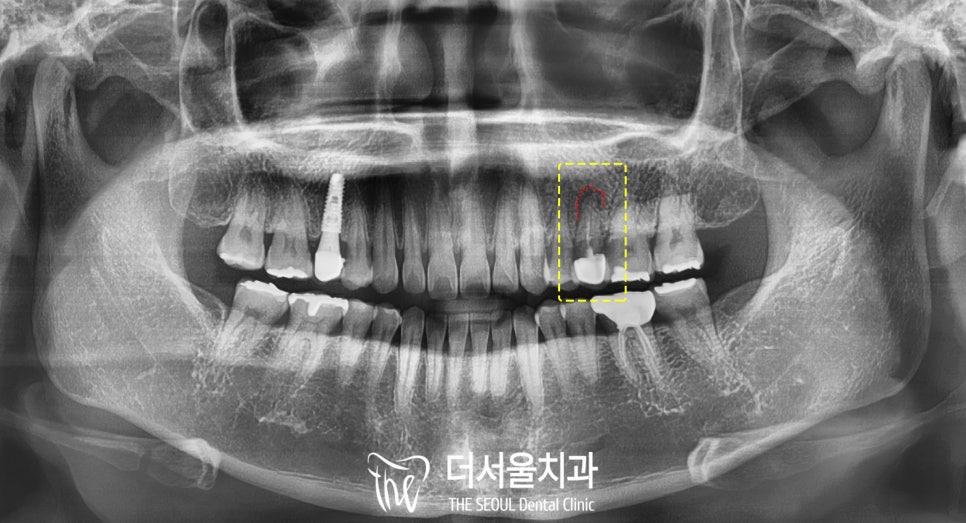

이 환자의 경우

예전에 다른 곳에서 한(이제는 사라져버린..)

오른쪽 위 작은 어금니 임플란트는

방향도 조금 기울어져 있어서

지속적인 관리가 필요한데

심지어 보철에 홀이 없는 타입이라

a/s가 힘듭니다.

만약 문제가 생기면

크라운 전체를 뜯어내고

손을 봐야 된다는 뜻이죠.

치료 기간 : 2024.03.05 ~ 2024.06.02